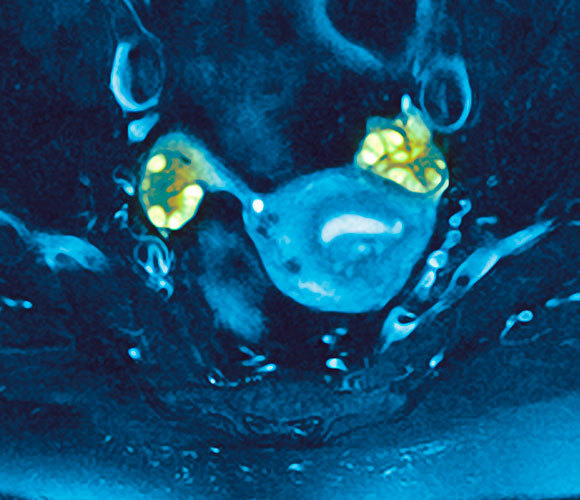

שחלות פוליציסטיות, צילום (צבוע) במיקרוסקופ אלקטרונים | מקור: PROFESSORS P.M. MOTTA & S. MAKABE / SCIENCE PHOTO LIBRARY

תסמונת השחלות הפוליציסטיות מתבטאת בתסמינים שונים אצל נשים שונות; לעיתים התסמינים משתנים עם הזמן, גם אצל אותה אישה עצמה. התסמונת נקראת כך בשל ריבוי זקיקים (ביציות בלתי מופרות) בשחלות, שכיום אפשר לראות אותן בעזרת בדיקת אולטרסאונד. בבדיקה רואים גם הגדלה של השחלות. אולם חשוב לציין שיש גם הפרעות אחרות הגורמות לשחלות פוליציסטיות (כגון תסמונת קושינג, שנתאר בהמשך). חשוב לשלול גם הפרעות הורמונליות אחרות (כגון בעיות בתפקוד בלוטת התריס, יותרת הכליה או יותרת המוח) שעלולות לגרום לאי-סדירות של המחזור, להשמנה ולתסמינים אחרים האופייניים גם לתסמונת זו.